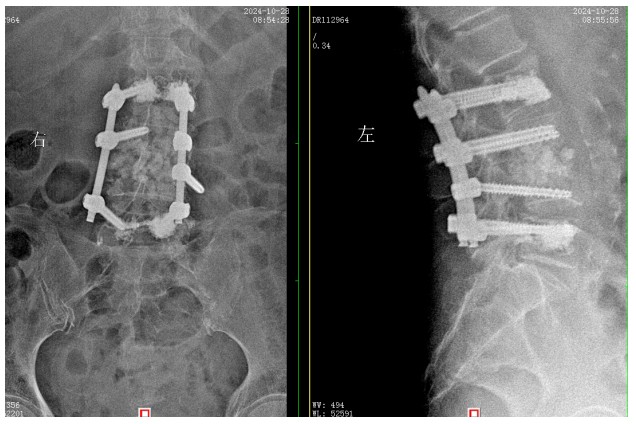

經(jīng)過積極充分的準(zhǔn)備,錢軍博士團(tuán)隊(duì)為患者成功實(shí)施了L3、L4脊柱結(jié)核病灶清除植骨融合內(nèi)固定術(shù),手術(shù)順利,術(shù)后患者腰腿痛癥狀明顯緩解,患者及家屬對(duì)治療效果非常滿意,對(duì)醫(yī)院的醫(yī)療技術(shù)以及優(yōu)質(zhì)的服務(wù)護(hù)理稱贊不已。